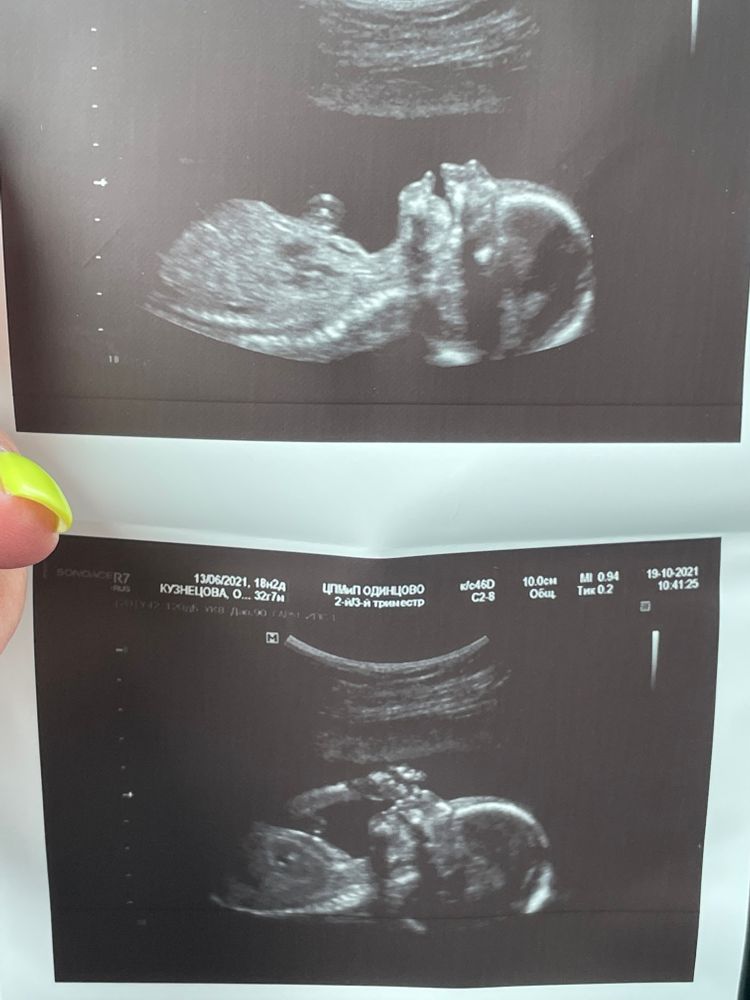

Наша красавица 💕 18.2

Ахаха ! Как прикольно)) правда как будто смеётся!! 😊😍

Очень классные фотки 😍 И отличная ШМ 💪

Какая прелесть-то🥰 а у нас есть фото, где малышка повернулась лицом и смотрит прям в "камеру"😃